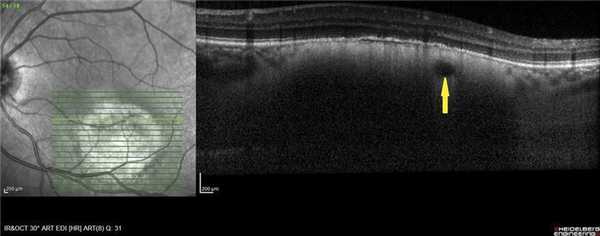

В 8 наблюдениях (толщина ГХ 1-3,15 мм) в зоне интереса визуализировали ампулообразное утолщение хориоидеи с «выстоянием» в сторону склеры (рис. 1). Полосу склеры в проекции максимальной толщины ГХ удалось зафиксировать в 3 случаях (толщина опухоли 1; 1,25 и 1,3 мм) (см. рис. 1). При анализе томограмм в режиме оттенков серого в зоне патологического очага у 25 пациентов, независимо от высоты ГХ, практически сразу выявили очертания относительно крупных сосудов под мембраной Бруха, диаметр их просвета варьировал от 65 до 559 мкм, (рис. 2). Следует отметить, что в зоне максимальной проминенции ГХ имели место сосуды меньшего диаметра, а по периферии опухоли - сосуды большего диаметра.

Рис. 1. ОКТ-горизонтальный срез через ГХ в зоне ее максимальной проминенции. Ампулообразное расширение хориоидеи (полоса склеры указана стрелками).

Рис. 2. ОКТ-горизонтальный срез. Крупный сосуд в толще ГХ (указан стрелкой).